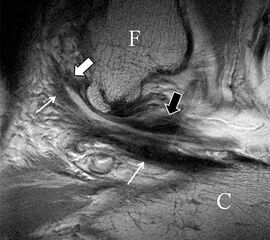

Der Ursprung des Ligamentum fibulocalcaneare liegt unmittelbar kaudal und dorsal des Ursprungs des Ligamentum fibulotalare anterius, so dass gehäuft kombinierte Verletzungen und auch ein gemeinsamer knöcherner Ausriss beobachtet werden. Nach kaudal dorsal verläuft das Band dann nach medial konvex unter die Peroneussehnen. Danach ist ein schräg deszendierender, gestreckter Verlauf bis zum calcanearen Ansatz abgrenzbar (Abb. 10). Dieser zu allen drei Standardebenen schräge Verlauf erschwert häufig die Diagnostik des LFC vor allem bei subtileren Verletzungen. Spezialprojektionen, die dem Bandverlauf orthograd folgen (entweder schräg coronar oder schräg sagittal) erleichtern auch hier die Diagnostik (Abb. 11) insbesondere nicht dislozierter Avulsionen. Assoziierte Verletzungen der Peroneussehnenloge müssen mit beurteilt werden, wobei neben Verletzungen der Sehnen und Sehnenscheiden die Beurteilung des Retinaculum peroneum superius und inferius wichtig ist. In einem Kollektiv von Patienten mit chronischen Außenbandinstabilitäten weisen 50% der Patienten eine Verletzung dieser Strukturen auf 5. Auch hier erleichtern hochauflösende Techniken die Diagnostik (Abb. 12).